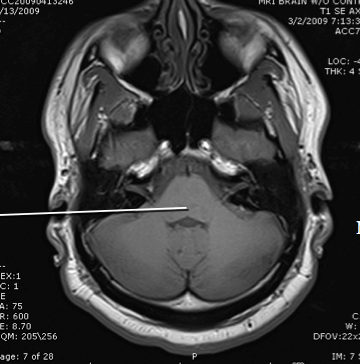

spinal cord

medulla

cerebellum

4th ventricle